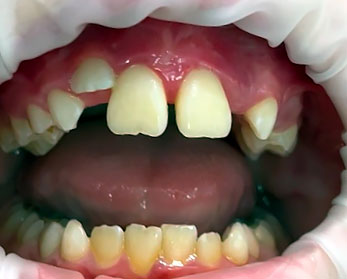

Контрольный осмотр через 14 дней после хирургического лечения

Жалобы отсутствуют.

Осмотр полости рта: композитно-проволочная шина стабильная. Окружающая без признаков воспаления, пальпация безболезненная. Зубы 1.1, 2.1 подвижность 1 степени, холодовая проба положительная. Определяются отложения зубного налета по десневому краю и в области шины.

Проведено снятие композитно-проволочной шины, полировка зубов.

Зубы 1.1, 2.1 подвижность отсутствует, диастема отсутствует, холодовая проба положительная. Определяются обильные отложения зубного налета. Окружающая слизистая гиперемирована. Признаки патологических десневых карманов отсутствуют. Признаки прорезывания зубов 2.2 и 2.4 (Рисунки 17, 18).

Рисунок 17. Клиническая картина через 6 месяцев после хирургического лечения.